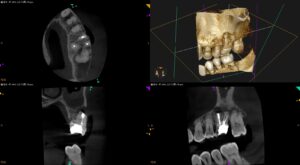

歯茎にできものができて腫れて痛い…〜#14 MB+DB Apicoectomy

紹介患者さんの治療。 主訴は、 歯茎にできものができて腫れて痛い… である。 ☆この後、検査画像が出てきます。不快感を感じる方は視聴をSkipしてください。 歯内療法学的検査(2025.8.19) PA(2025.8.1 … 続きを読む 歯茎にできものができて腫れて痛い…〜#14 MB+DB Apicoectomy